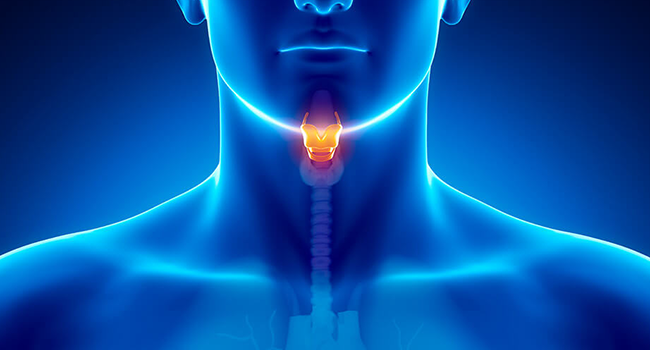

4. Sistemik ve Metabolik Hastalıklar

- Diyabet

- Vitamin eksiklikleri

- Tiroid hastalıkları

4. Sistemik Hastalıkların Tedavisi

Diyabet, vitamin eksikliği veya tiroid bozuklukları düzenlendiğinde koku-tat duyusu iyileşebilir.